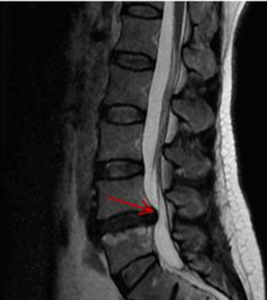

Figuur 1. Patiënt met hernia op niveau L4–L5, maar zonder lage rugpijn. Dit benadrukt dat structurele afwijkingen zichtbaar op MRI niet altijd samengaan met klachten of pijnervaring.